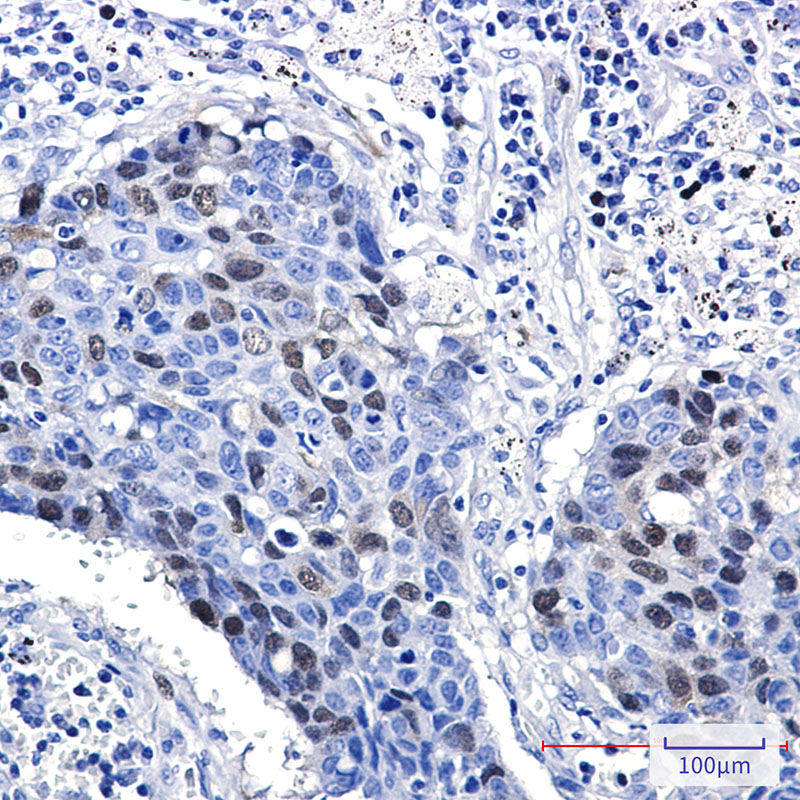

- Immunohistochemistry analysis of paraffin-embedded Human lung cancer using Cyclin A2 antibody.High-pressure and temperature Sodium Citrate pH 6.0 was used for antigen retrieval.